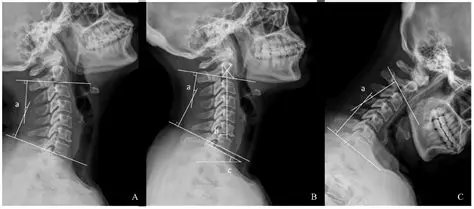

Causes of Blackened Top Portion on Radiographs